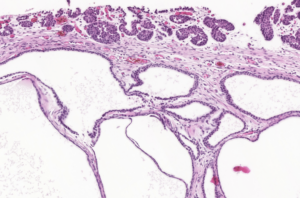

The polyps found in the bladder mucosa consist of a core of proliferative connective tissue covered by surface epithelium. This surface epithelium can form nests of hyperplastic urothelial cells in the lamina propria, known as Brunn’s nests, or undergo metaplasia to a mucus-secreting, glandular epithelial type, leading to a condition called CYSTITIS GLANDULARIS. These resulting polypoid masses may have a broad-based or pedunculated structure, occurring most frequently in the cranioventral bladder wall. Chronic haematuria, often unresponsive to antimicrobial therapy, is a common observation in cases of chronic polypoid cystitis. This bleeding is often associated with the breakdown of polyps, potentially promoting urine retention and bacterial introduction, thus establishing a cyclic pattern of infection, proliferation, and inflammation.

Histologically, our case had in lamina propria, occasionally extending from mucosa, multiple hyperplastic tortuous glands that were often cystic dilated. They were lined by one to multiple layers of uniform cuboidal or columnar epithelial cells, occasionally surrounded by a few layers of urothelial cells. They had no evident atypia. The lamina propria where they were immersed contained a few plasma cells, lymphocytes, neutrophils and rare histiocytes.